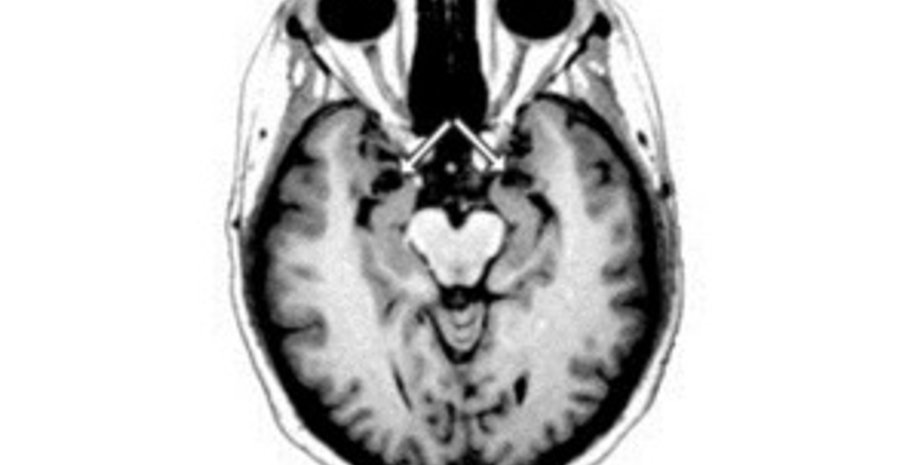

Как пишет Washington Post, Хоукинс страдала частичной потерей памяти: она знала, как ее зовут, и что ей 54 года. В частную вашингтонскую больницу женщина была доставлена с диагнозом "обезвоживание и почечная недостаточность". Ранее Хоукинс жила в приюте, а свою жизнь до приюта женщина не помнила.